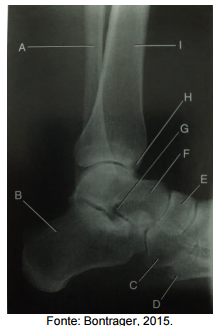

Assinale a alternativa que apresenta a correta correlação entre a indicação e a estrutura na imagem tomográfica.